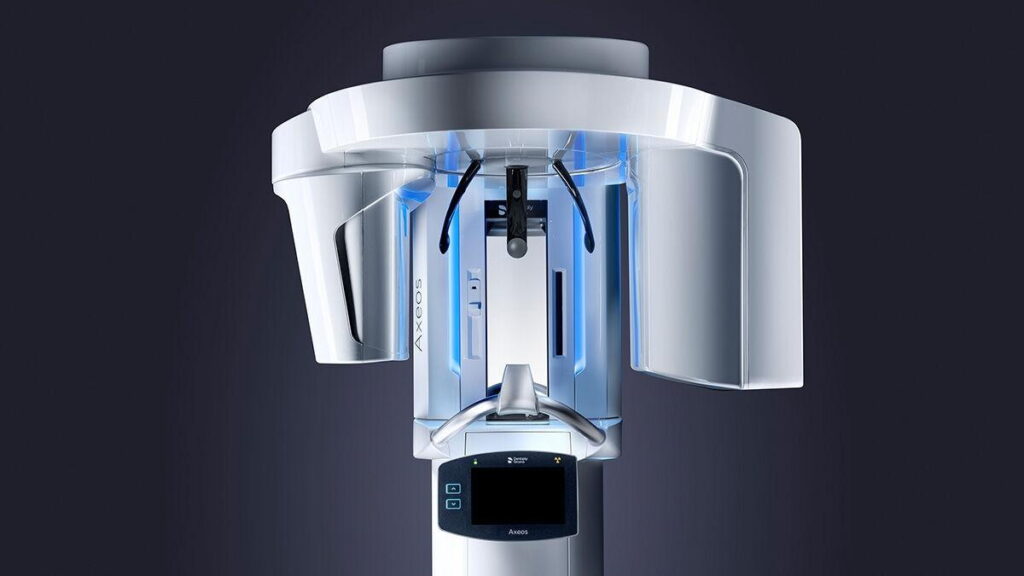

3D Intraoral Scanning

Replacing Guesswork with Precision

Traditional impressions rely on materials that distort, pressure that varies, and interpretation that changes from case to case.

Our 3D intraoral scanner captures your teeth digitally, in real time, with micrometer‑level accuracy.

What this changes for patients:

- No physical impressions

- Immediate visualization of your current condition

- Clear explanation of treatment options on screen

- A shared understanding before any decision is made

Patients consistently say they feel more in control when they can see what is being discussed — not imagine it.

3D intraoral scanners eliminate variables such as material distortion, pressure differences, and manual interpretation. What we see digitally is what guides the treatment, allowing both dentist and patient to reference the same visual information at every stage.